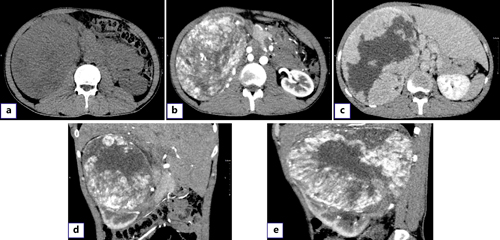

A 28-year-old male was admitted with pain in the right abdomen and gross hematuria. His blood pressure and temperature were normal. Palpation of the abdomen revealed a large mass in the right upper abdomen with a hard texture and poor mobility. The patient had no previous history of gastrointestinal diseases and no family history of tumors. Leukocytes (12.19 × 103/μL) and hypersensitive C-reactive protein (118.73 mg/L) were increased. Urinalysis showed increased RBC (24,158.3/HPF) and white blood cell count (612.2/μL). Enterococcus faecalis was found in urine culture. Contrast-enhanced computed tomography showed a 175 × 130-mm heterogeneous mass in the upper pole of the right kidney, with multiple low-density and nodular calcification shadows. The arterial mass was significantly enhanced and was supplied by the right renal artery without metastasis (Fig. 1a–e).